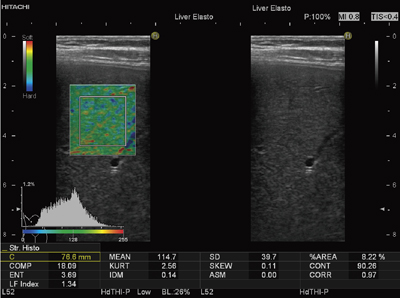

Strain Histogram計測は,ROI内の任意に指定された領域の相対ひずみ値のヒストグラム(頻度分布のグラフ)を表示するもので,テクスチャー解析によるReal-time Tissue Elastography画像の特徴量の算出も可能である(図3)。

図3 Strain Histogram計測ソフトによる画像解析